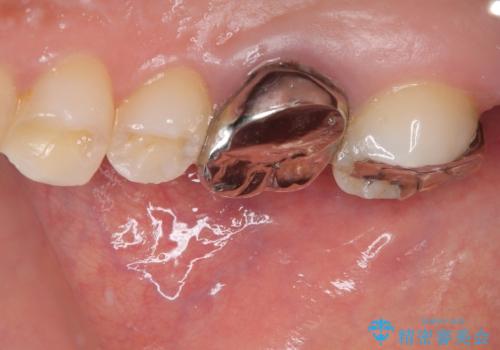

インプラント希望部位は右下第一大臼歯と第二大臼歯です。

しかし、噛み合わせの相手である右上の第二大臼歯が、長期間噛み合う歯がなかった影響で**挺出(歯が下に伸びてくる状態)してしまっており、このままではインプラントを埋入して被せもの(上部構造)を入れるためのスペースが不足している状態でした。